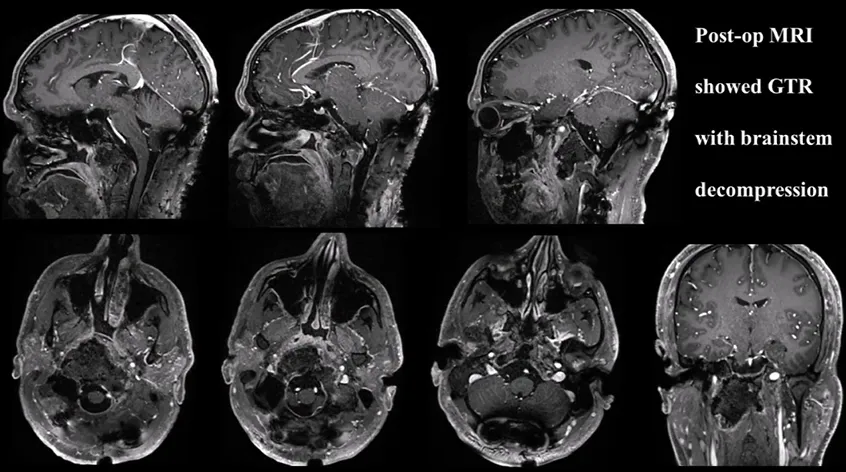

术后计算机断层扫描(CT)与磁共振成像(MRI)复查显示肿瘤已被完全切除,脑干及延髓所受的占位性压迫得到有效解除。术后病理学检查证实为典型脊索瘤。在术后恢复期间,患者的吞咽功能得到改善,颈部疼痛亦得以缓解。术后第八周,他接受了质子束放射治疗。

▼术后磁共振成像(MRI)显示肿瘤获得完全切除,且脑干压迫得到解除